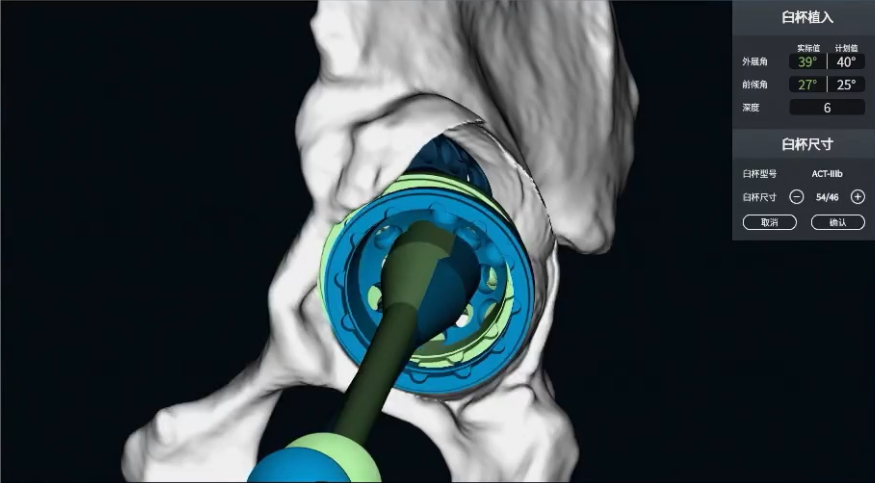

VTS辅助假体植入

VTS系统辅助补块植入